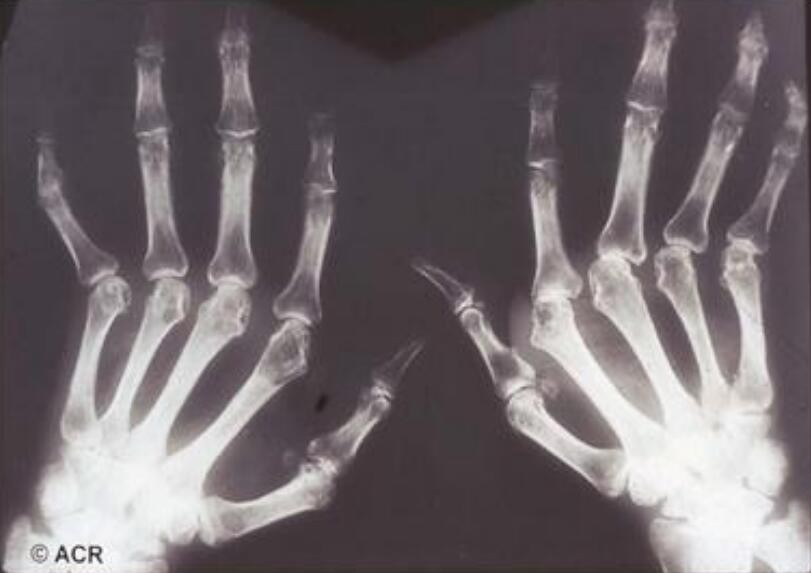

風(fēng)濕吃蜂王漿還是有一定好處的,風(fēng)濕大多有關(guān)節(jié)病變和癥狀,會有紅腫、疼痛以及功能受損等多方面炎癥的表現(xiàn)。蜂王漿中的王漿酸有很強(qiáng)的殺菌消炎的作用,可以清除身體內(nèi)的一些細(xì)菌,對于炎癥和紅腫都有一定的緩解作用。